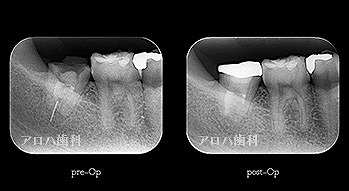

case1

初回根管治療

1年予後

治療回数1回